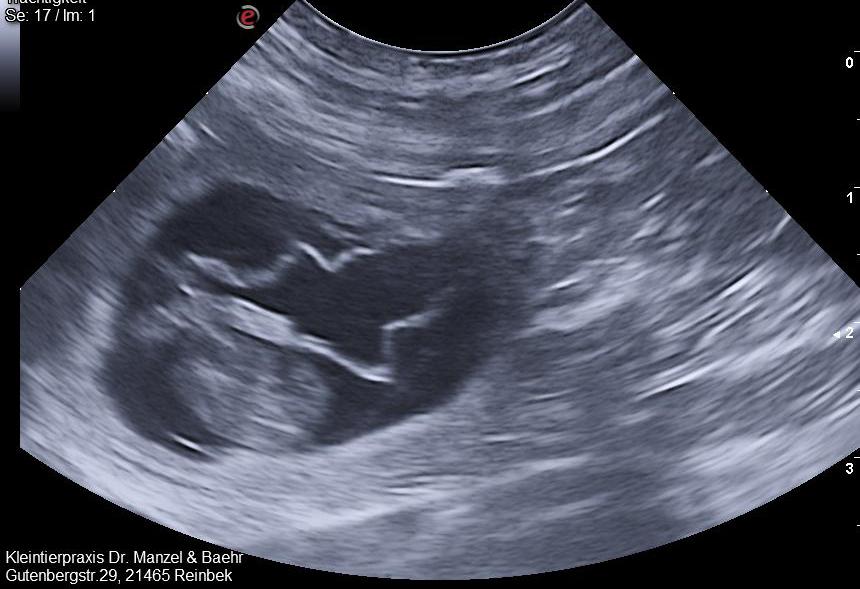

Heute war ich mit Mango zum Ultraschall bei meinem Haustierarzt und ich könnte platzen vor Freude! Mango bekommt Welpen. Mein Tierarzt hat 5 Früchte gezählt. Ich hatte es ja schon vermutet. Sie ist seit der Rückkehr aus unserem Urlaub extrem kuschelig, hat irgendwie so einen sanften Blick, ist sehr ruhig und ist ständig auf der Suche nach etwas Essbarem. Fanta hatte es eigentlich auch schon gepetzt. Sie schüffelte plötzlich immer wieder an Mangos Intimteil.